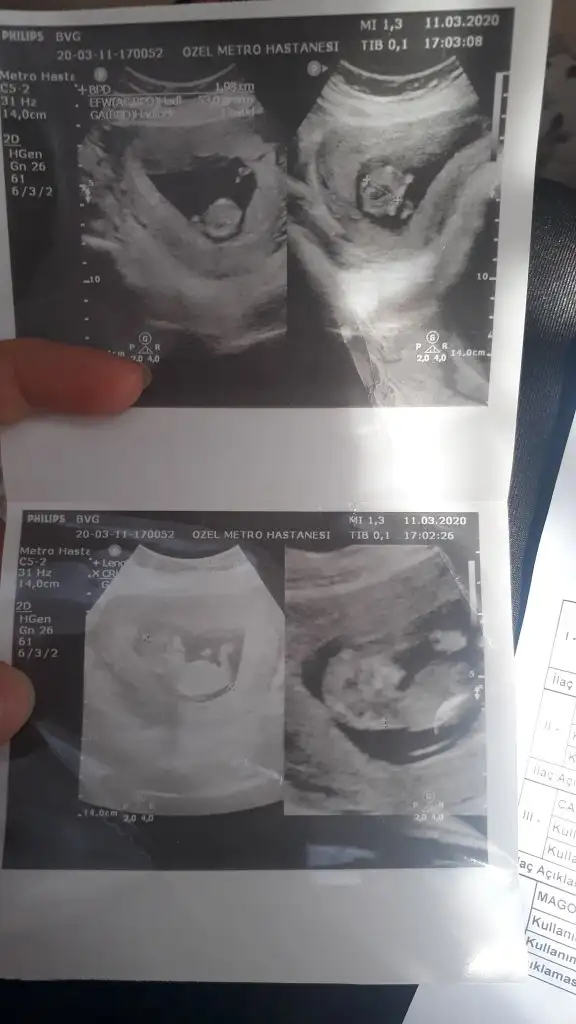

Ikra meyra canim bakar mısın Bi cinsiyet tahmini 15 haftalık

Kız gibielimdeki tüm usg görüntüleri bunlaryeterli olur mu ki tahmin için